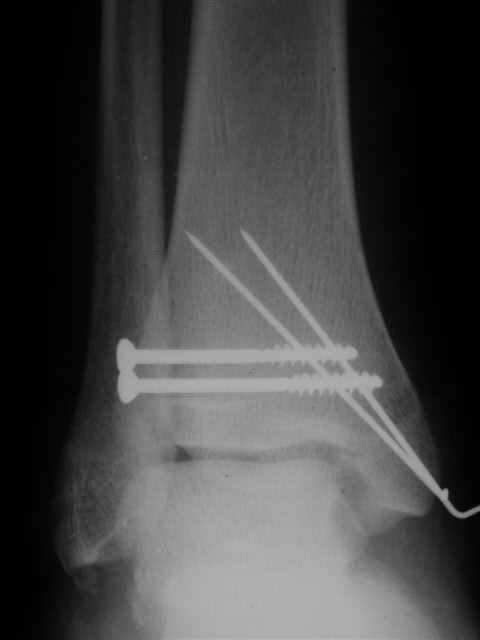

В первом письме я упомянул о закрытом повреждении правого голеностопного сустава, эверсионно-пронационный механизм травмы - перелом внутренней лодыжки( поперечный, на уровне суставной щели) и отрывной перелом бугорка Chaput. После обработки открытых переломов бедра и большеберцовой кости в эту же сессию перелом внутренней лодыжки фиксировал двумя расходящимися спицами, бугорок Chaput двумя тягловыми винтами 3,5 мм. Раны заживают благополучно. Учитывая повреждение наружной группы мышц, активное разгибание в голеностопном суставе ограничено. Пассивная + пассивно-активная мобилизация голеностопного сустава с физиотерапевтом.

Я предупреждал, что ничего сверхъестественного. Каюсь, что одна из спиц прошла несколько дальше, чем нужно было, но главное - перелом стабилизирован и больной работает суставом в полном объёме, несмотря на представленную раннее травму коленного сустава.